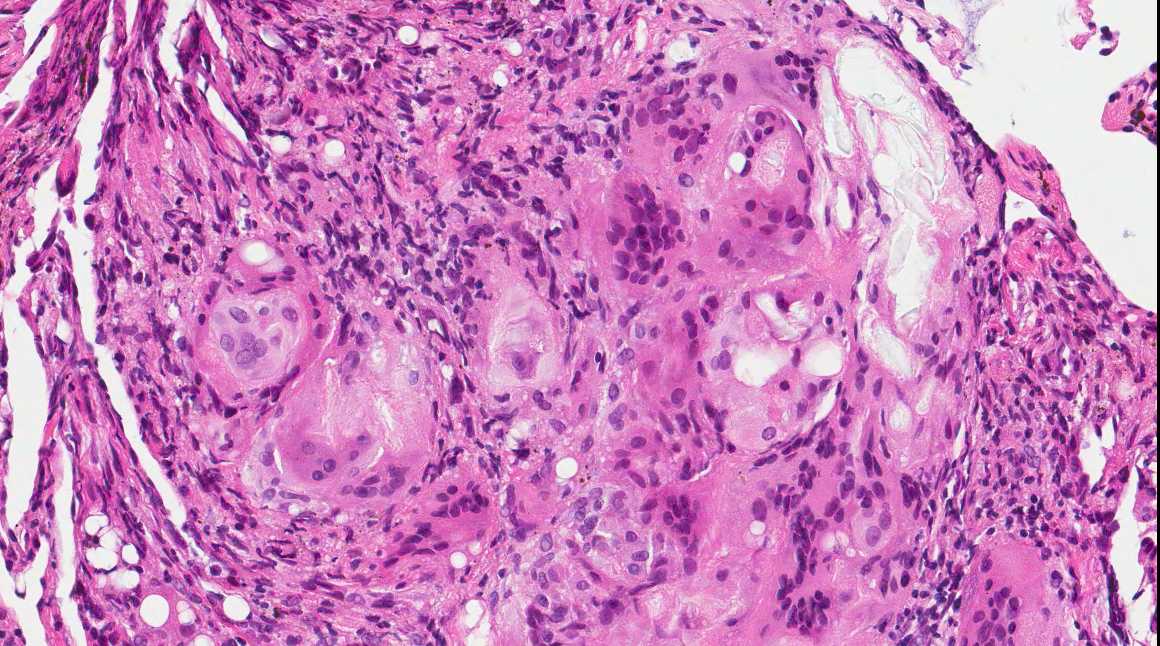

A 71 year old man with recent history of meningitis presented with recurrent episodes of pneumonia. High resolution CT scans showed crazy paving and tree in bud images. The patient underwent a transbronchial biopsy.

Diagnosis: Aspiration with granulomatous bronchiolitis and lipoid pneumonia

Aspiration of particulate matter, traditionally observed at autopsy, has also been described in debilitated patients, who often have a history of recurrent pneumonia, which is often unrecognized (Am J Surg Pathol 2007;31:752, Am J Surg Pathol 2010;34:1456). It usually (88%) shows bronchiolitis obliterans organizing pneumonia, often with multinucleated giant cells, acute bronchopneumonia / bronchiolitis or suppurative granulomas. Foreign material is usually but not always present (Am J Surg Pathol 2011;35:426).

The differential diagnosis of pulmonary granulomatous inflammation is broad and requires special stains, culture and clinical correlation (Ann Diagn Pathol 2003;7:127, Histopathology 2007;50:289).

Lipoid pneumonia is often an incidental postmortem finding associated with debilitating disease. The lipid may be exogenous (from nasal sprays or inhalation of other lipid containing substances) or endogenous (bronchial obstruction).

A 71 year old man with recent history of meningitis presented with recurrent episodes of pneumonia. High resolution CT scans showed crazy paving and tree in bud images. The patient underwent a transbronchial biopsy.

Diagnosis: Aspiration with granulomatous bronchiolitis and lipoid pneumonia

Aspiration of particulate matter, traditionally observed at autopsy, has also been described in debilitated patients, who often have a history of recurrent pneumonia, which is often unrecognized (Am J Surg Pathol 2007;31:752, Am J Surg Pathol 2010;34:1456). It usually (88%) shows bronchiolitis obliterans organizing pneumonia, often with multinucleated giant cells, acute bronchopneumonia / bronchiolitis or suppurative granulomas. Foreign material is usually but not always present (Am J Surg Pathol 2011;35:426).

The differential diagnosis of pulmonary granulomatous inflammation is broad and requires special stains, culture and clinical correlation (Ann Diagn Pathol 2003;7:127, Histopathology 2007;50:289).

Lipoid pneumonia is often an incidental postmortem finding associated with debilitating disease. The lipid may be exogenous (from nasal sprays or inhalation of other lipid containing substances) or endogenous (bronchial obstruction).